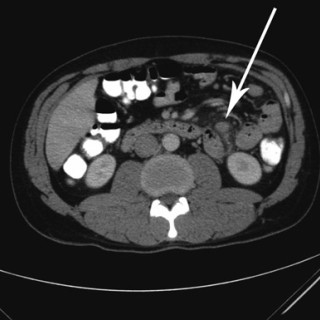

HACEK er et akronym som refererer til en gruppe taksonomisk ulike bakterier med en rekke fellestrekk. Det står for Haemophilus parainfluenzae, Aggregatibacter (A aphrophilus, A actinomycetemcomitans), Cardiobacterium spp., Eikenella corrodens og Kingella kingae (1, 2). Alle disse har en tendens til å forårsake endokarditt, men de var tidligere lite kjent fordi de er vanskelige å få til å vokse. HACEK-endokarditt havnet derfor i gruppen kulturnegative endokarditter. Fremdeles forblir mange av disse endokardittene kulturnegative. Bakteriene er små, gramnegative staver tilhørende den...